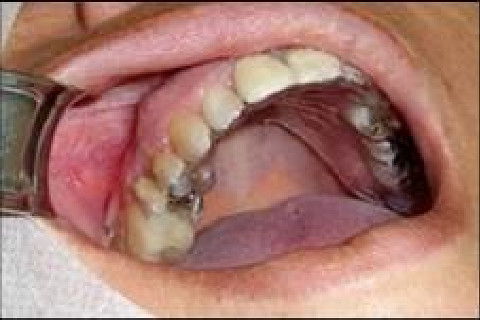

PACIENTE: A.C.V, de quarenta e dois anos de idade, sexo feminino, portadora de Diabetes Mellitus tipo II,controlada, procurou a Odontoclínica da UNIFESO para reabilitação protética fixa na maxila direita na região do primeiro molar superior direito ausente. O planejamento proposto foi de uma reabilitação com a utilização de implante osseointegrado.

Atualmente, a evolução alcançada no campo da Implantodontia permite a utilização de implantes osseointegráveis e próteses sobre implantes na resolução de diferentes tipos de edentulismo de forma mais eficiente e conservadora, quando comparado ao uso de próteses convencionais. A alta taxa de previsibilidade, quando associado a um planejamento criterioso, e as inúmeras vantagens para o paciente, são alguns fatores que permitem disponibilizarmos esta modalidade terapêutica inclusive nas clínicas de graduação, contanto que o paciente apresente condições locais e sistêmicas favoráveis e aja um acompanhamento rigoroso do caso por profissionais experientes e devidamente qualificados. O objetivo deste trabalho é relatar um caso clínico onde a instalação de um implante osseointegrável foi o tratamento eleito para o edentulismo unitário maxilar posterior (região do elemento 16) de uma paciente da clínica de graduação da Faculdade de Odontologia do UNIFESO, com indicação prévia para realização de prótese fixa convencional. O uso do implante osseointegrável neste caso representou a opção mais conservadora e econômica, evitando o desgaste desnecessário de dentes adjacentes ao espaço protético para a substituição do elemento perdido, exigir um menor número de consultas, além de permitir neste caso em particular melhores condições de higienização e manutenção em relação a uma prótese fixa suportada por dentes, sendo um procedimento que pode ser agregado de forma segura e definitiva.